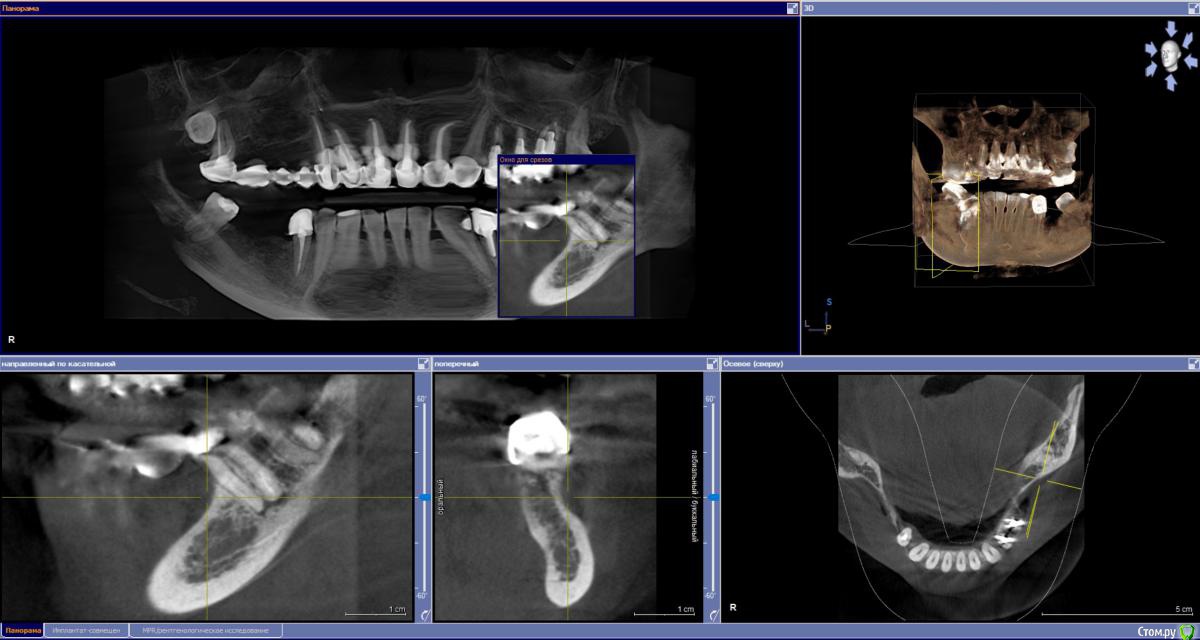

sabik Опубликовано 13 марта, 2019 Поделиться Опубликовано 13 марта, 2019 Хотела б услышать мнение по поводу возможности установки имплантов, ходила в несколько клиник, все говорят разное, общее только то, что на КТ видно, что нет кости вообще, проблема с верхней пазухой,нужна операция лор, еще вопрос можно ли повторить этот мост наверху при отсутствии трех зубов? Не хотят браться за меня нигде Еще беспокоит тупая ноющая боль время от времени, на снимке слева внизу, причину не находят. Подскажите, есть ли зубы на удаление, и какие проблемы видно в общем? Ссылка на комментарий

sabik Опубликовано 14 марта, 2019 Автор Поделиться Опубликовано 14 марта, 2019 Болтается мост сверху, на снимке слева, и беспокоит тупая боль снизу на этой же стороне, жую почти 2 года другой стороной, нужно менять коронки и где возможно установить импланты. Хочу услышать мнение профессионалов по снимку, что можно сделать в моей ситуации. По КТ кости не хватает нигде. Ссылка на комментарий

sabik Опубликовано 23 марта, 2019 Автор Поделиться Опубликовано 23 марта, 2019 Выкладывайте срезы КТПо инструкции с сайта не смогу выложить срезы, нет соответствующей папки (Dicom), но сделала скриншоты (прикреплены к сообщению) проблемных мест в программе. Если не совсем то, скажите, как лучше сделать скриншоты (или видео). Очень нужно мнение специалистов! Ссылка на комментарий

kramer Опубликовано 23 марта, 2019 Поделиться Опубликовано 23 марта, 2019 Источник боли с правой стороны на нижней челюсти пока неясен. Что касается верх право, чтобы ставить имплантаты, надо предварительно делать синус-лифт, до синус-лифта надо приводить пазуху в порядок с помощью ЛОР врача Ссылка на комментарий

sabik Опубликовано 23 марта, 2019 Автор Поделиться Опубликовано 23 марта, 2019 Источник боли с правой стороны на нижней челюсти пока неясен. Что касается верх право, чтобы ставить имплантаты, надо предварительно делать синус-лифт, до синус-лифта надо приводить пазуху в порядок с помощью ЛОР врача Спасибо, что ответили! Возможно ли поставить импланты снизу справа? А слева какая ситуация, есть ли кисты. удалять надо зубы или нет, все говорят разное просто, очень сложно понять кто прав(( Ссылка на комментарий

Nazim_NV86 Опубликовано 23 марта, 2019 Поделиться Опубликовано 23 марта, 2019 Возможно ли поставить импланты снизу справа? Возможно. А слева какая ситуация, есть ли кисты. удалять надо зубы или нетПроблемы есть. Нужно во рту смотреть и томограмму. Вы срезы не те выкладываете. Этот Galileos только с диска читается. Ссылка на комментарий

sabik Опубликовано 2 апреля, 2019 Автор Поделиться Опубликовано 2 апреля, 2019 Предлагают два варианта постановки имплантов справа внизу: первый вариант - поставить 2 импланта вместо 5 и 6 зуба, с подсадкой кости, расщеплением гребня, а второй вариант- 2 импланта вместо 5 и 7 зуба, с подсадкой кости только на 5 зубе, а на место 7-го имплант сразу ровно поставленный, и позже мост . 7 зуб живой, но с наклонном, боль есть тупая, говорят может он один там и нагрузка идет на него, не знаю, из-за этого может болеть он временами или нет, перидонтальная щель расширена чуть тоже. Как считаете, какой вариант имплантации лучше? Ссылка на комментарий